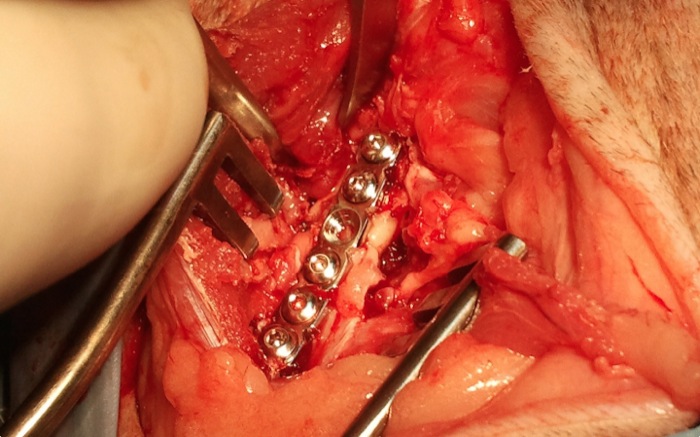

Se colocan, con abordajes que se alienan desde la piel el fémur y el ileon, las placas correspondientes. El fémur presenta una amplia zona diafisaria media solo con la cortical posterior intacta lo que impide la colocación de tornillos en mas de un tercio de la longitud de la placa.

Aún así se consigue una estabilidad completa y fuerte del hueso dañado.